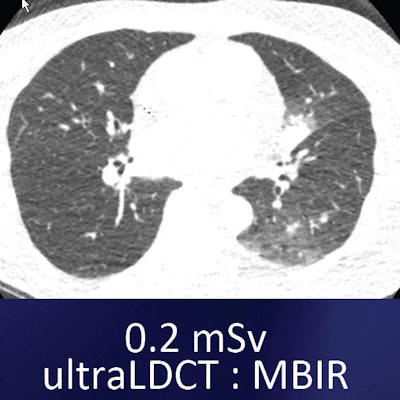

For example, one commercially available MBIR protocol (Veo, GE Healthcare) has shown an impressive ability to reduce noise and improve contrast and spatial resolution, she said. The technique, cleared by the U.S. Food and Drug Administration (FDA) in 2011, uses advanced modeling of system statistics and optics to increase spatial and contrast resolution while permitting vastly lower radiation doses -- as low as 0.2 mSv -- in the lungs.

Compared with low-dose and ultralow-dose filtered back projection (FBP), ultralow-dose MBIR significantly reduced objective noise (p < 0.01). Still, compared with low-dose FBP, ultralow-dose MBIR and ultralow-dose FBP showed reduced image sharpness (p < 0.001).

The ultralow-dose images were blotchy and pixelated, "however, the performance of [ultralow-dose] MBIR was significantly superior to that of [ultralow-dose] FBP for the detection of noncalcified pulmonary nodules" (p = 0.002) and did not significantly affect screening CT results, according to Yamada and colleagues.

"Using low-dose CT with filtered back projection as truth, ultralow-dose CT detected all of the calcified nodules" 4 mm and larger, Kazerooni said. And when it came to the 184 noncalcified nodules in the study ... the ultralow-dose technique with MBIR picked up more nodules than the ultralow-dose technique with FBP, with a true-positive fraction of 94%, she added. For all nodules 4 mm and larger, ultralow-dose CT picked up nearly 95% of all nodules compared to the reference standard.